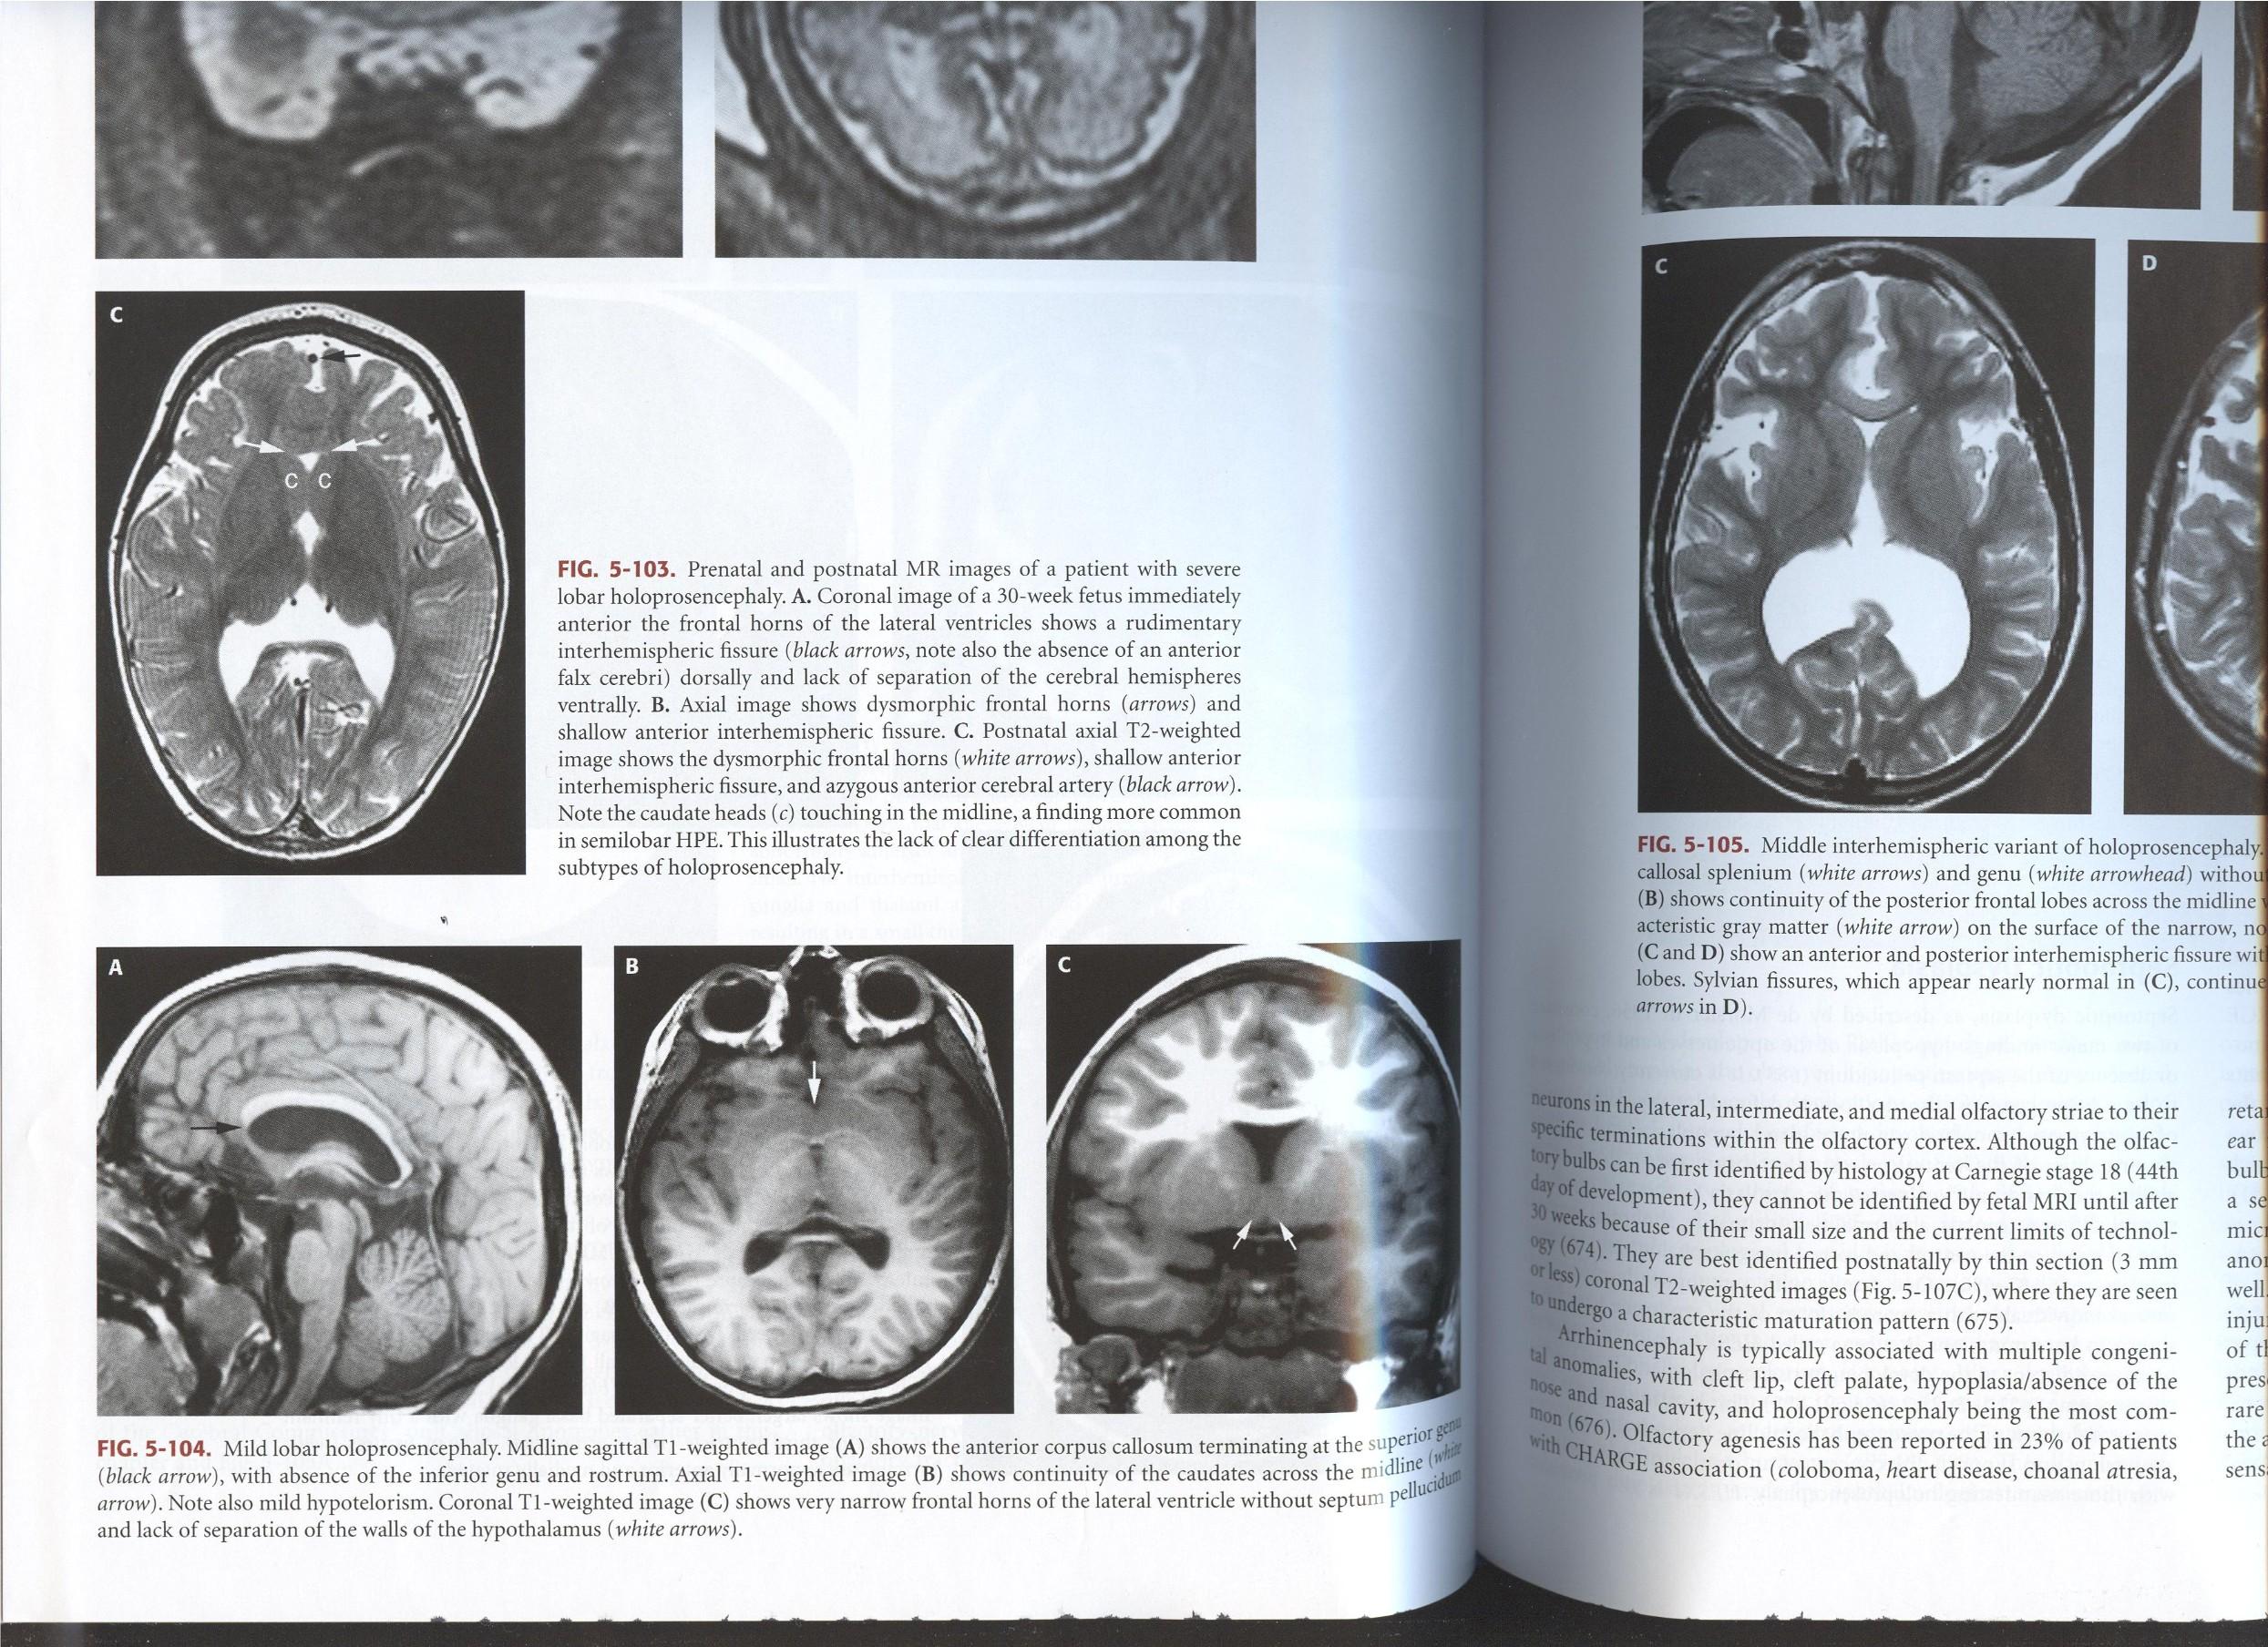

Alobar

Most severe, complete lack of “cleavage”, fused thalami.

Semilobar

“ in between” with separated occipital lobes

Lobar Mild, often only anterior frontal lobe fused, with separate thalami

Sweep the Midline:

“Comma shaped Corpus Callosum with abnormal mid body…”

Syntelencephaly: Midline CC “lack of cleavage”

Middle Interhemispheric “MIH” Variant of Holoprosencephaly